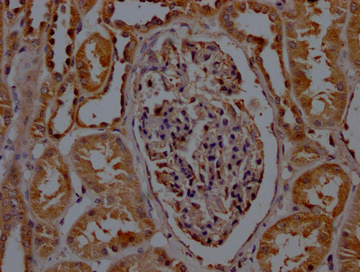

IHC image of CSB-PA020907LA01HU diluted at 1:200 and staining in paraffin-embedded human kidney tissue performed on a Leica BondTM system. After dewaxing and hydration, antigen retrieval was mediated by high pressure in a citrate buffer (pH 6.0). Section was blocked with 10% normal goat serum 30min at RT. Then primary antibody (1% BSA) was incubated at 4°C overnight. The primary is detected by a Goat anti-rabbit polymer IgG labeled by HRP and visualized using 0.05% DAB.